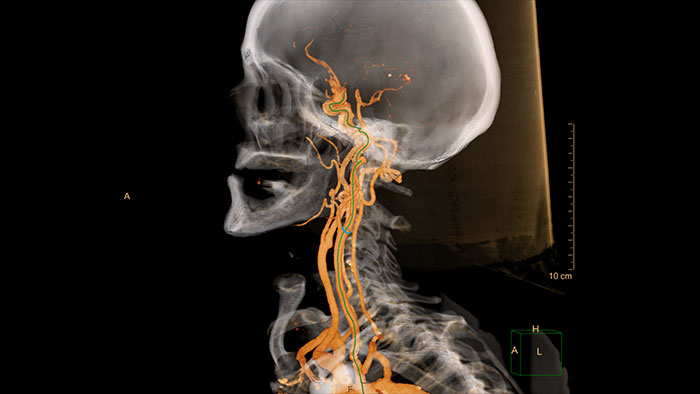

Comprehensive vascular analysis planning

Designed to examine and quantify different types of vascular lesions from CTA and MRA scans. It accommodates different modes of inspection, allows labeling different vascular lesions, and helps navigating through multiple findings. Demonstrated to reduce the post-processing time by 50% when compared to manual Head & Neck CT angiography (CTA) analysis*.

Benefits

* Ardley N et al. Efficacy of a new post processing workflow for CTA head and neck. ECR 2013 / C-1760.